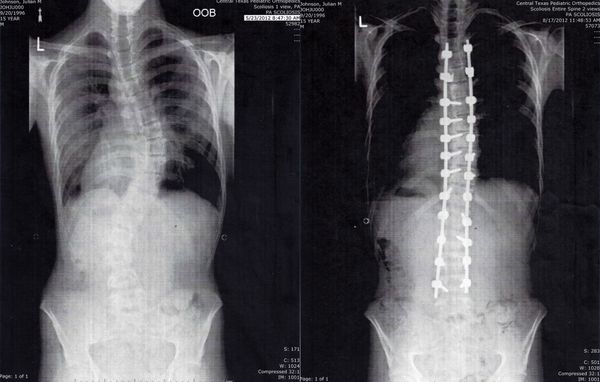

I remember reading about Marfan Syndrome in my high school biology class, the textbook featuring a picture of a skinny boy looking like a deer caught in the headlights. Since getting diagnosed at age five, I’ve been dissatisfied with the cold, clinical imagery surrounding the connective tissue disorder. Even You, Metal Back is an exploration of the intersection of physical pain, mental health, religion, and healing. A self-portrait, if you will, unearthing anxieties around corporality while living with this chronic condition.